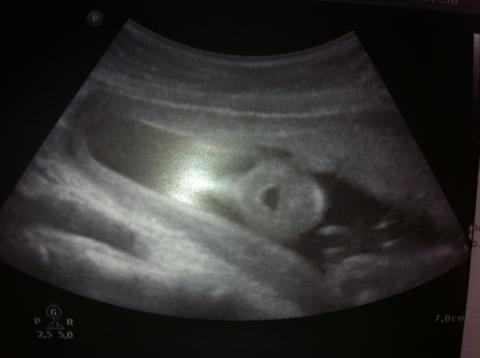

Pro větší náhled klikněte na obrázek

Dobrý den, je mi 20let, 20+6tt, byla jsem dnes v rámci genetického vyš. na ultrazvuku. Nejprve paní doktorka chválila, říkala jak je vše v normě a jak má být, ale potom si všimla, že miminko má po celou dobu vyšetření otevřenou pusinku. Prý to není normální a jsme objednáni za týden na další kontrolu. Nikde jsem nemohla najít co by to mohlo znamenat, nebo z jakého důvodu? Můžete mi poradit co by mohlo být špatně? Testy na DS vyšly negativní. Přikládám foto. Děkuji za Váš názor.

Miminko bežne otvára a zatvára ústočká, ale nestretla som sa za 11 rokov praxe, že by počas celého UZ vyšetrenia malo len otvorenú pusinku a nehýbal s ňou.